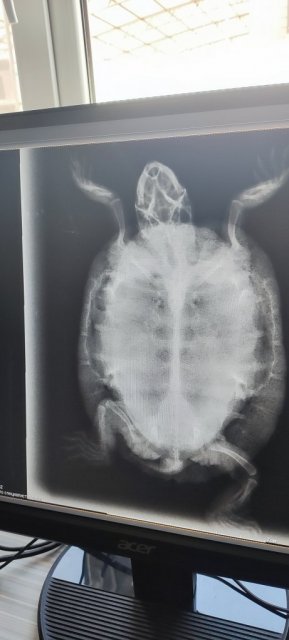

Консультанты moth Ваше имя: Мария Локация: Москва Опубликовано: 26 марта 2024 Консультанты Опубликовано: 26 марта 2024 @Владимир* если будете делать рентген, то нужны проекции 1 и любая 2 или 3. Лёгкие видно только на проекциях 2 и 3. 1 это общее состояние скелета и внутренних органов, лёгкие там не видно.

Владимир* Ваше имя: Владимир Локация: Георгиевск Опубликовано: 24 апреля 2024 Автор Опубликовано: 24 апреля 2024 @moth Сделали рентген, врач работал первый раз с черепахой. Нашли почти единственного кто согласился. С лёгкими сказал всё в порядке. У правой передней ноги может быть предвывех. Так же делал переднее фото. Сказал что черепаха сильно обезвожена и надо поколоть физраствор. Один кубик в обе передние лапы 2-3 раза в день. Он не мастер черепах, сделал вывод по общему состоянию.

Владимир* Ваше имя: Владимир Локация: Георгиевск Опубликовано: 24 апреля 2024 Автор Опубликовано: 24 апреля 2024 (изменено) Рекомендация для настройки рентгена, 3 фото. Я это имел ввиду под передним. @moth Изменено 24 апреля 2024 пользователем Владимир*

Консультанты moth Ваше имя: Мария Локация: Москва Опубликовано: 24 апреля 2024 Консультанты Опубликовано: 24 апреля 2024 @Владимир* Вы самую важную и нужную проекцию в итоге не сфотографировали. Я по этой не могу Вам ничего сказать ни про лёгкие ни про пневмонию. Нужен тот снимок "спереди". Можете его в клинике получить? Пневмония может на весь организм оказывать влияние